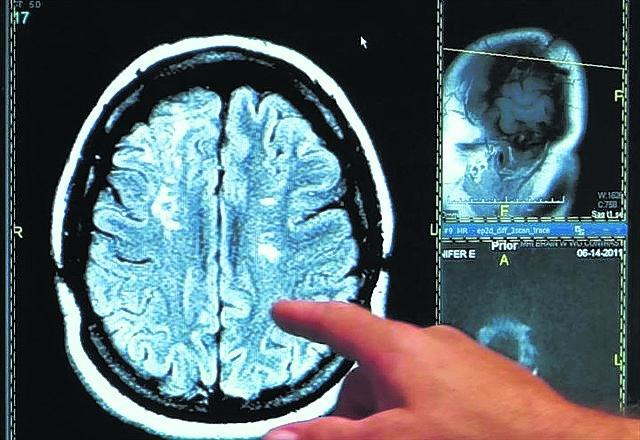

Hace décadas, se daba por sentado que el mayor período de desarrollo cerebral sucedería en los primeros años de vida, pero en ese entonces no contábamos con las herramientas necesarias para mirar dentro del cerebro y determinar con mayor precisión su desarrollo en las diferentes etapas de la vida. Los grandes avances en métodos tales como la RMN estructural y funcional nos permiten entender que no todo termina de desarrollarse en los primeros años de vida, sino que el desarrollo cerebral continúa hasta pasados los 20 años. La adolescencia se trata de una de las etapas de transición más importantes en la vida del ser humano y se caracteriza por un ritmo acelerado de crecimiento y cambios.

Desarrollos desparejos y disparatados subyacen a esas conductas. La región prefrontal del cerebro, que se ocupa de las llamadas funciones ejecutivas y del control de impulsos, se va desarrollando lentamente y a un ritmo parejo a través de la adolescencia. A medida que los niños crecen y se convierten en adolescentes y luego en adultos, el desempeño en tareas de control de impulsos va mejorando, logrando gradualmente resistirse a las recompensas inmediatas, considerando el largo plazo, a través de esta maduración lineal de esta región cerebral.

Por el contrario, otras regiones (subcorticales) relacionadas con la emoción, la motivación y la recompensa, presentan un desarrollo rápido en la adolescencia temprana, sobrepasando la lenta maduración de las regiones prefrontales. Dado que las interacciones entre la corteza prefronal y estas regiones subcorticales juegan un rol fundamental en la regulación de la conducta, la disparidad entre los componentes emocionales e intelectuales en la toma de decisiones adolescente genera decisiones sesgadas y vulnerables.